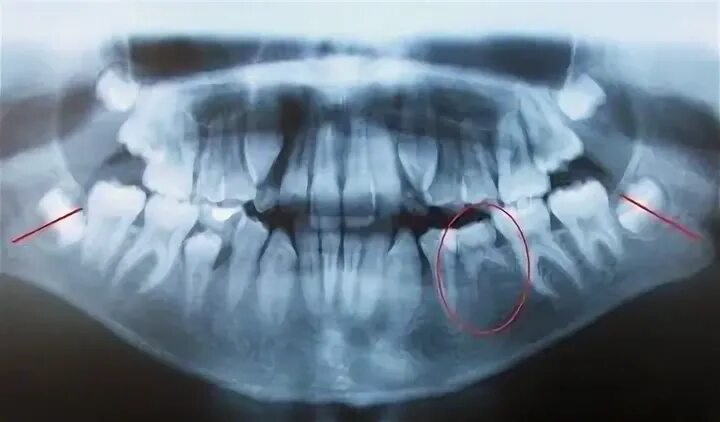

У ребенка нет зачатка постоянного зуба